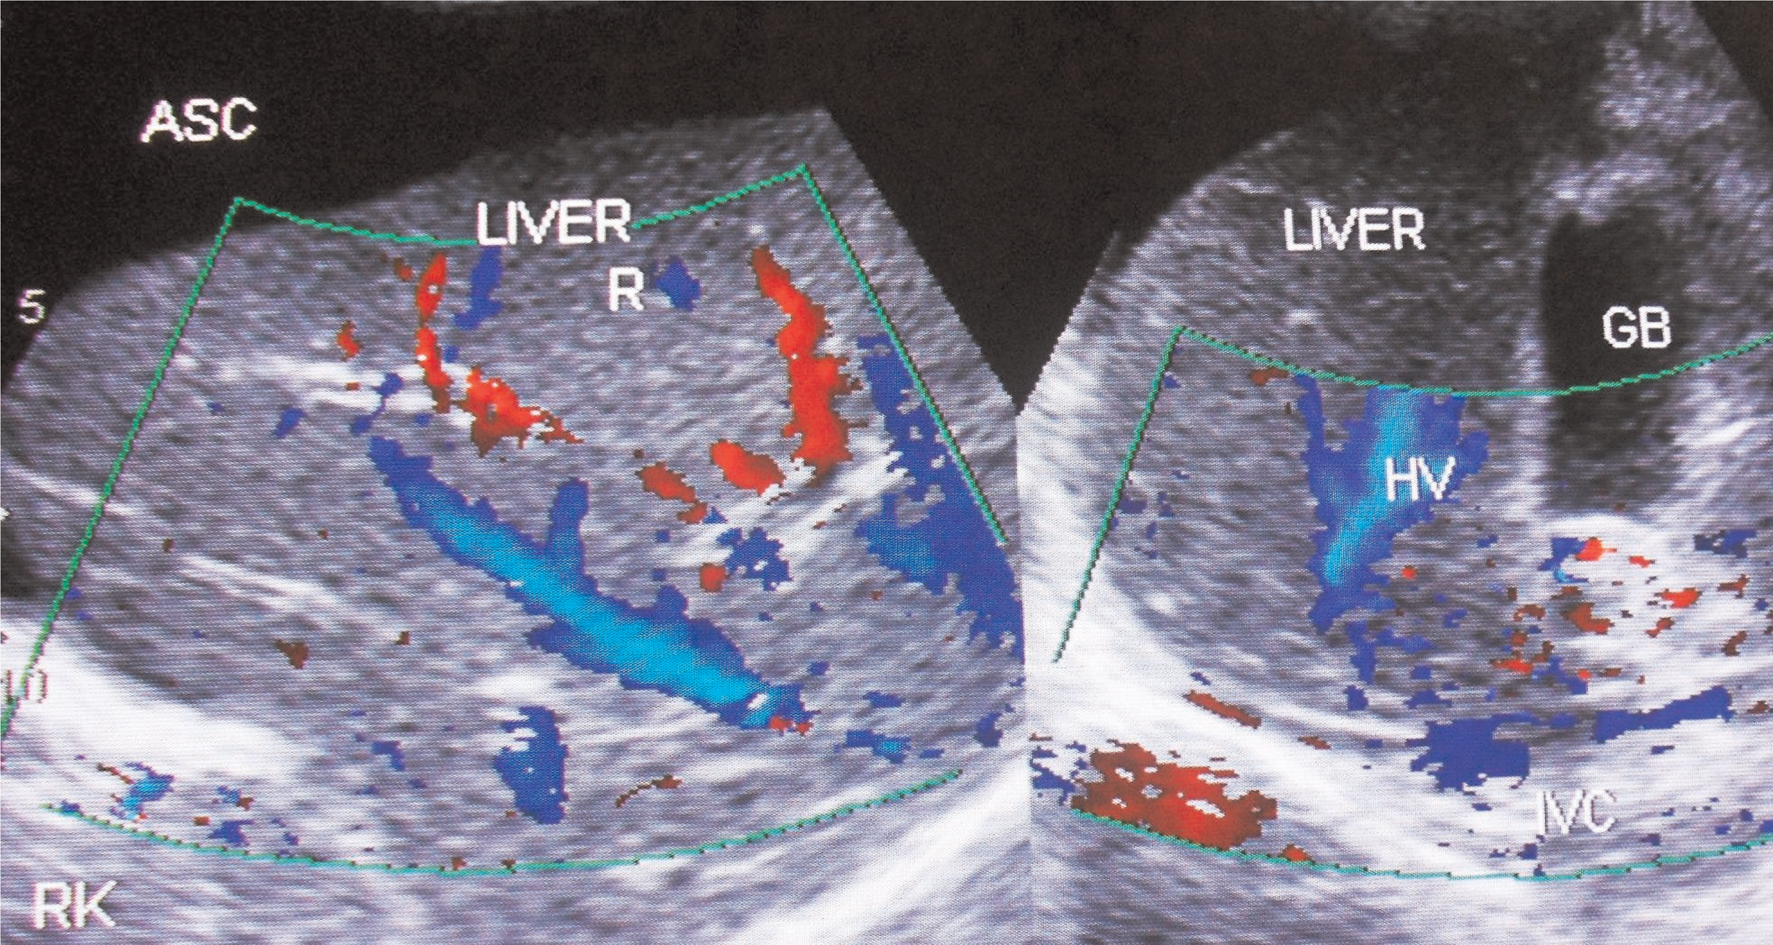

Fig 3

Figure 3. Hepatic vena cava syndrome: Ultrasonography of a young patient with ascites showing localized stenosis of upper segment of IVC with distal dilated segment of the IVC filled with recent and old organized thrombi. ASC, ascites; IVC, inferior vena cava; OT, organized thrombus; RA, right atrium; T, thrombus. (Copyright: Santosh Man Shrestha).